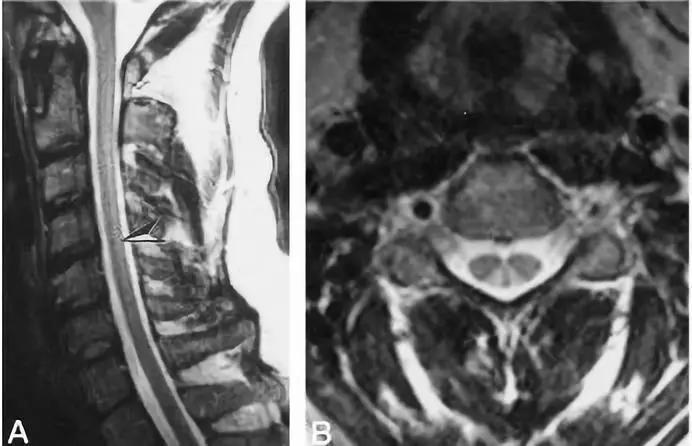

无骨折脱位型脊髓损伤 (Spinal cord injury without radiographic abnormality,SCIWORA) 是指在 X 线或 CT 检查未发现骨折或脱位的脊髓损伤,主要见于儿童,SCWORA 的创伤机制包括过度伸展、屈曲、牵引和脊髓缺血损伤。

MRI:

脊髓长节段或短节段病灶,颈胸髓常见

T2WI 高信号;T1WI 低信号